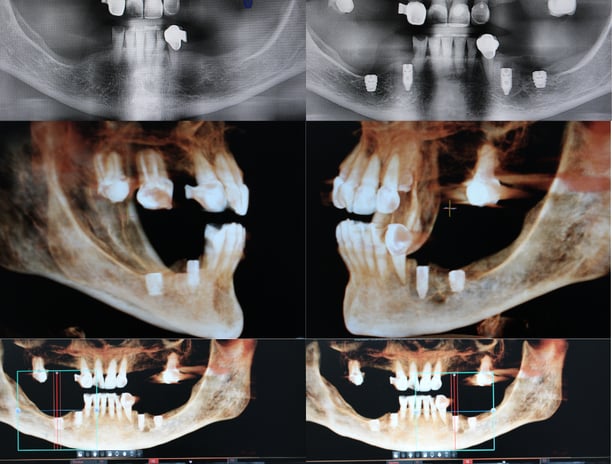

Comprometidos con la excelencia, enseñamos técnicas innovadoras en implantología y cirugía oral, formando a los futuros referentes del sector. Ofrecemos diferentes posibilidades de formación: online y presencial, damos formación para aquellos doctores que quieren aprender a hacer cirugía guiada sin fabricarse sus propias guias, y por otro lado damos formación para los doctores que quieren aprender las dos cosas, realizar cirugía guiada, y fabricarse sus propias guías quirúrgicas.

Curso teórico (preparamos a los doctores para adquirir todos los conocimiento necesarios para realizar cirugía guiada en sus clínicas)

Módulo casos clínicos nivel avanzado (presentación de 30 casos)

Curso teórico (preparamos a los doctores para adquirir todos los conocimiento necesarios para realizar cirugía guiada en sus clínicas) formación en ventas del producto

Modulo planificación, diseño, impresión y montaje de guías quirúrgicas (adquiere todos los conocimientos para poder prepararte tus propios casos)